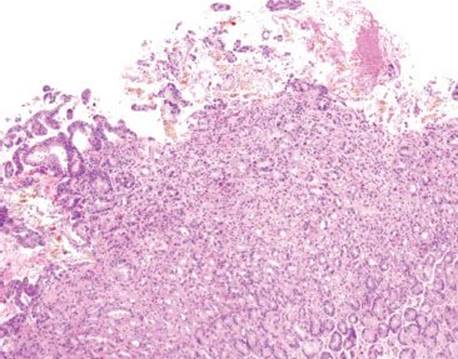

Gastric iron deposition is seen in up to 3.8% of upper tract biopsies (Fig. 2.228).23,24,183–185 In a study of 500 gastric biopsies, the deposition was demonstrated in three generalized patterns. Pattern A (also referred to as “nonspecific gastric siderosis”) was the most common subpattern and involved 2.2% of specimens (Figs. 2.229 and 2.230). This subpattern was associated with prior mucosal microhemorrhages, and the subtle depositions were predominantly identified within macrophages and stromal cells of the lamina propria. Pattern B (also referred to as “iron pill gastritis”) was seen in 0.8% of the biopsies and was consistently associated with ferrous sulfate therapy. This deposition was coarse and crystalline and predominantly identified in the extracellular and most superficial aspect of the biopsy (Figs. 2.231–2.234). In this subpattern, the background mucosa had a reactive gastritis/gastropathy pattern with erosions, ulcerations, and fibrino-inflammatory exudate common. In a separate study of 1,300 gastric biopsies, a similar “iron pill gastritis” injury pattern was detailed.184 This latter group reproduced the identical iron deposits in the laboratory by oxidizing ferrous sulfate tablets, providing clear evidence for the iron origin of these deposits. The mechanism of injury is a bit unclear in this subpattern. Some speculate that the iron pill has a direct caustic effect on the adjacent mucosa, whereas others suggest that the iron deposits may simply colonize previously injured mucosa. Pattern C (also referred to as “gastric glandular siderosis”) was the least common pattern, involving 0.6% of the specimens. This subpattern was associated with iron overload settings, such as hereditary hemochromatosis and multiple blood transfusions. The characteristic deposits were subtle, uniform, and identified in the deep antral and oxyntic glands (Figs. 2.235–2.239). The iron deposits can be highlighted blue with a Prussian blue iron special stain. Recognition is important to help prevent further injury and potential stricture formation (pattern B), to suggest pertinent iron overload evaluation (pattern C), and to avoid overdiagnosing the marked reactive epithelial change as dysplasia.

Figure 2.231 Iron pattern B/“iron pill gastritis”. In this dramatic case, coarse crystalline iron deposits are seen on the mucosa and within the luminal debris (arrowheads). A prominent reactive gastritis/gastropathy pattern is also seen in the background.